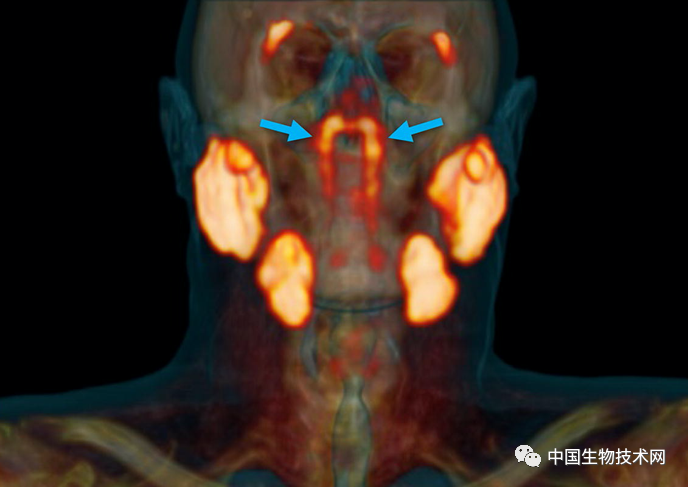

“管状腺”结构 , 用蓝色箭头表示 , 其他主要唾液腺用橙色表示 。 图片来源:荷兰癌症研究所

该研究通讯作者、荷兰癌症研究所的放射肿瘤学家Wouter Vogel解释说:“人有三大唾液腺(腮腺、下颌下腺和舌下腺) , 但新发现的不是在那里 。 据我们所知 , 鼻咽中仅有的唾液腺或粘液腺在显微镜下很小 , 多达1000个腺体均匀分布在整个粘膜上 。 所以 , 想象一下 , 当我们发现这些时有多惊讶吧 。 ”

Vogel团队新发现的要大得多 , 它显示出似乎是先前被忽视的一对腺体 , 表面上看是第四大主要唾液腺 , 位于鼻咽后部、上颚上方 , 靠近人类头部的中心 。

该研究第一作者 , 阿姆斯特丹大学的口腔外科医生Matthijs Valstar说:“这两个新发现的区域也具有唾液腺的其他特征 。 根据它们的解剖位置(在咽鼓管上方) , 我们称之为‘管状腺’(tubarial glands) 。 ”

在对所有100例患者进行的PSMA PET/CT扫描 , 均发现存在这些管腺 , 并且对两名尸体(一男一女)的身体检查也显示出神秘的双侧结构 , 从宏观上可见引流管开口朝向鼻咽壁 。